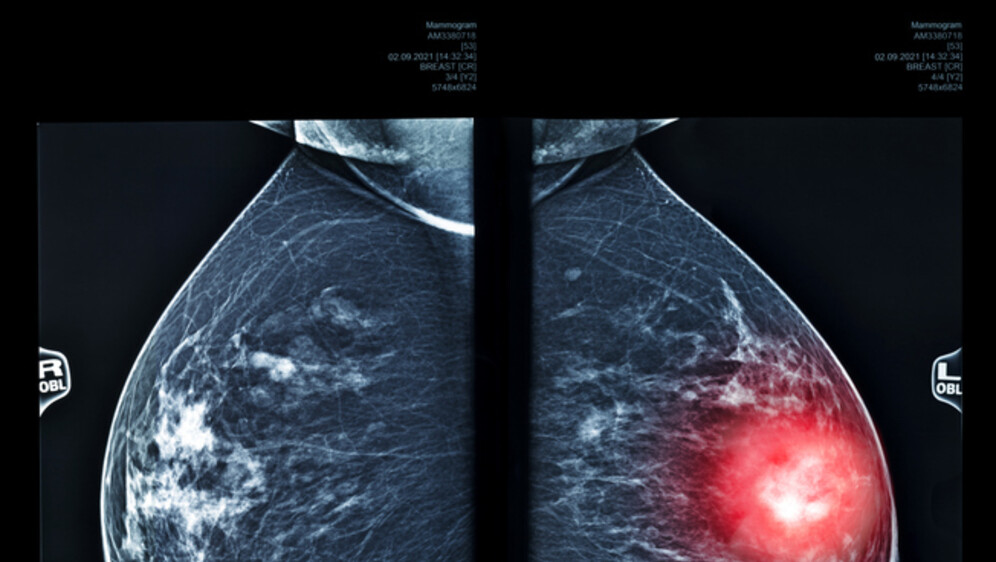

Rentgenska snimka dojki, ilustracija

Rentgenska snimka dojki, ilustracija Foto: Getty Images